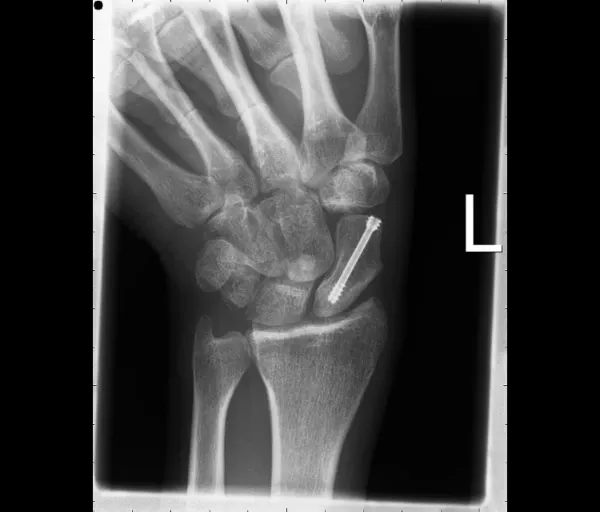

Scaphoidfractuur

Wat is het?

Het scaphoid is een handwortelbeentje aan de duimzijde van de pols. Een breuk ontstaat meestal door een val op de hand. Scaphoidbreuken geven soms weinig klachten, waardoor ze gemakkelijk gemist worden. Het scaphoid heeft een zwakke bloedvoorziening, vooral in de proximale pool. Hierdoor is er risico op:

- non-union/pseudartrose (breuk groeit niet aan elkaar)

- en hierdoor later artrose van de pols (SNAC-wrist)

Operatief

Nodig bij:

- Proximale poolfracturen (slechte bloedvoorziening)

- Verplaatste breuken

- Non-union of malunion

Behandelingen:

- Schroeffixatie: vergroot de kans op genezing en verkort de gipsperiode

- Percutane techniek voor recente, niet-verplaatste breuken (klein sneetje)

- Open ingreep voor verplaatste breuken

- Bij non-union/malunion: aanvulling met botgreffe uit het bekken of het spaakbeen